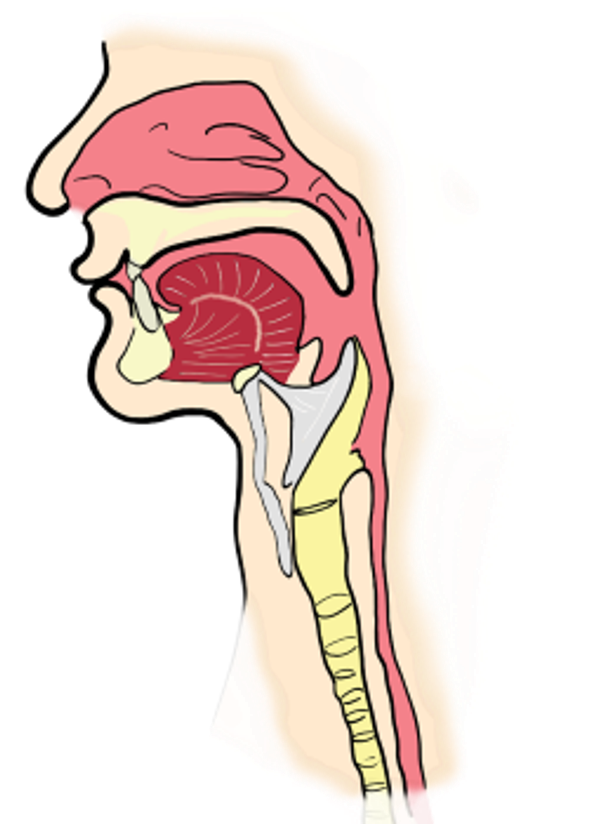

Je denkt misschien dat de hik ontstaat in je keel, omdat het zo kenmerkende geluid ervan daar vandaan komt, maar de oorzaak van de hik zit een flink stuk lager. Hik ontstaat namelijk door een samentrekking van je middenrif, ook wel diafragma genoemd. Dit middenrif – een spier met een peesblad – fungeert als scheiding tussen de borstkas en de buikholte en ligt net onder de longen. Het helpt ons bij het ademhalen; als het middenrif naar beneden beweegt, krijgen de longen ruimte en wordt er lucht via de neus en mond in de longen gezogen. Beweegt het middenrif naar boven dan ademen we de lucht weer uit.

Over de beweging van het middenrif denken we niet na; het gebeurt automatisch via een signaal uit de hersenen. En daar zit ook direct het probleem: als je middenrif vanuit de hersenen een signaal krijgt dat het een krachtige beweging naar beneden moet maken, komt er veel lucht in de achterkant van de keel terecht. Dit heeft een plotselinge drukverandering tot gevolg. Hierdoor klapt de keel heel kort even dicht en dat geeft het kenmerkende hikgeluid. De vraag is echter wel wat nu de precieze oorzaak is van dat signaal uit de hersenen.